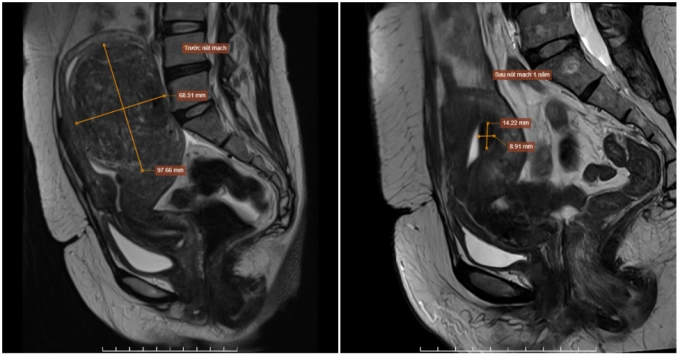

Hai năm trước, chị Lan phát hiện khối u xơ tử cung khoảng 4 cm nhưng không điều trị. Nay rối loạn kinh nguyệt kéo dài, chị đến Bệnh viện Đa khoa Tâm Anh Hà Nội chụp MRI cho thấy u xơ tăng lên tới 9,7×6,8 cm nằm trong lớp cơ tử cung, thành sau đáy tử cung, đẩy lồi niêm mạc tử cung. Bác sĩ chẩn đoán u có thể tăng sinh mạch mạnh, thuộc nhóm FIGO 2 – dễ gây rong kinh và đau bụng dữ dội khi hành kinh.

PGS.TS.BS Nguyễn Xuân Hiền, Trung tâm Chẩn đoán hình ảnh và Điện quang can thiệp, chỉ định người bệnh điều trị u xơ tử cung bằng phương pháp nút mạch thay vì cắt bỏ tử cung. Nút mạch giúp giảm thể tích khối u, kiểm soát lượng máu kinh, tránh thiếu máu do mất máu mạn tính, ảnh hưởng chất lượng cuộc sống, bảo tồn tử cung và tránh phẫu thuật, người bệnh hồi phục nhanh.

Theo bác sĩ Hiền, nút mạch là phương pháp ít xâm lấn, an toàn, hiệu quả cho nhiều phụ nữ bị u xơ tử cung. Bác sĩ dùng các ống thông đi vào động mạch, đẩy chất gây tắc để ngắt nguồn dinh dưỡng nuôi khối u xơ, từ đó u teo nhỏ, giảm dần và hết các triệu chứng đau bụng hay rong kinh. Can thiệp chỉ để lại vết rạch nhỏ 2 mm trên da đùi sau đó lành lại trong vòng một tuần, không để lại sẹo.

Trước đây, những bệnh nhân có u xơ tử cung kích thước lớn thường phải phẫu thuật để bóc tách u nhưng dễ bị chảy máu nếu u nằm dưới niêm mạc, dẫn đến phải cắt tử cung. Hiện, công nghệ nút mạch với sự hỗ trợ của hệ thống robot chụp mạch, giúp bác sĩ điều trị thành công những khối u kích thước lớn, không cần phẫu thuật, ít biến chứng sau điều trị và vẫn bảo toàn tử cung, có thể làm mẹ.